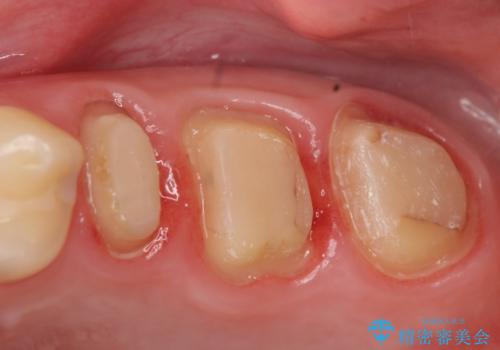

- 左上の歯が痛くてものが咬めないといらっしゃった方の症例です。

左上6は自発痛および持続痛を認めたため根管治療後、オールセラミッククラウンによる補綴を行いました。

左上7は冷水痛のみだったため、慎重に虫歯の除去を行い症状がないことを確認後、オールセラミッククラウンによる補綴を行いました。

左上5は再根管治療後、オールセラミッククラウンによる補綴を行いました。